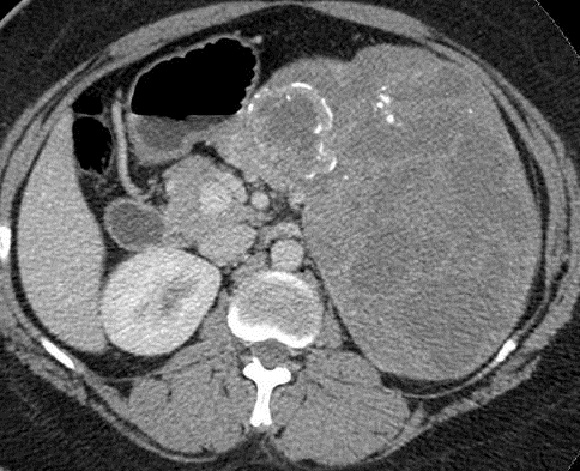

Image

radiologique TDM d'une kyste hydatique active

isthmique du pancreas type I pure avec

aspect lesionnel de masse hypodense de contenue

liquidienne homogene a paroi lisse , regulier situe

au corp du pancreas |

|

Aspect lesionnel de

formation kystique ovalaire homogene hypodense avec

paroie nette , lisse , regulier d'une kyste

hydatique active de type I de Gharbi . Image

radiologique TDM avec contrast intraveineuse coupe

axiale . Signe de rehaussement de sa paroi peut en

s'observe |